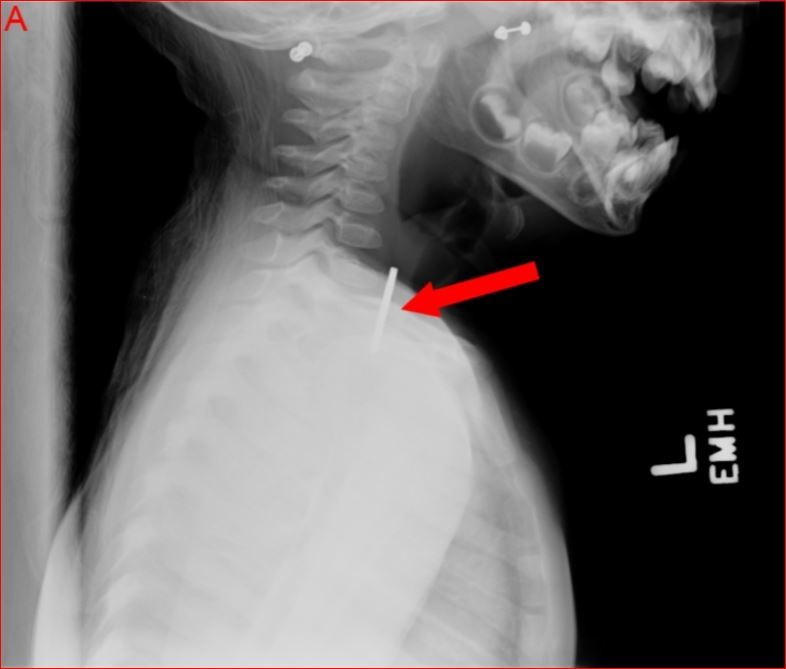

Do a 2-view (posterior anterior PA and later) neck xray and chest xray.

It confirms the location of the foreign body and distinguishes btwn a coin and battery (the latter can cause performation in just a few hours).

Coin is seen a homogenous object with a sharp, crisp edge; the bilaminar structure of a button battery causes a “double-ring” sign)

Child aspiration- battery versus coin?

Coin - homogenous with sharp crisp edge

Child aspiration (coin or battery)?

button battery

“double-ring” sign

This patient has no stridor, wheezing or respiratory distress and the lateral radiograph indicates the foreign body is in the esophagus rather than the airway.

In addition, an esophagel coin appears linear on lateral x-ray, a tracheal coin appears linear (project on end in the PA view) in the PA view.

Coin in esophagus versus trachea

an esphagel coin appears linear on lateral x-ray, a tracheal coin appears linear (project on end in the PA view) in the PA view.